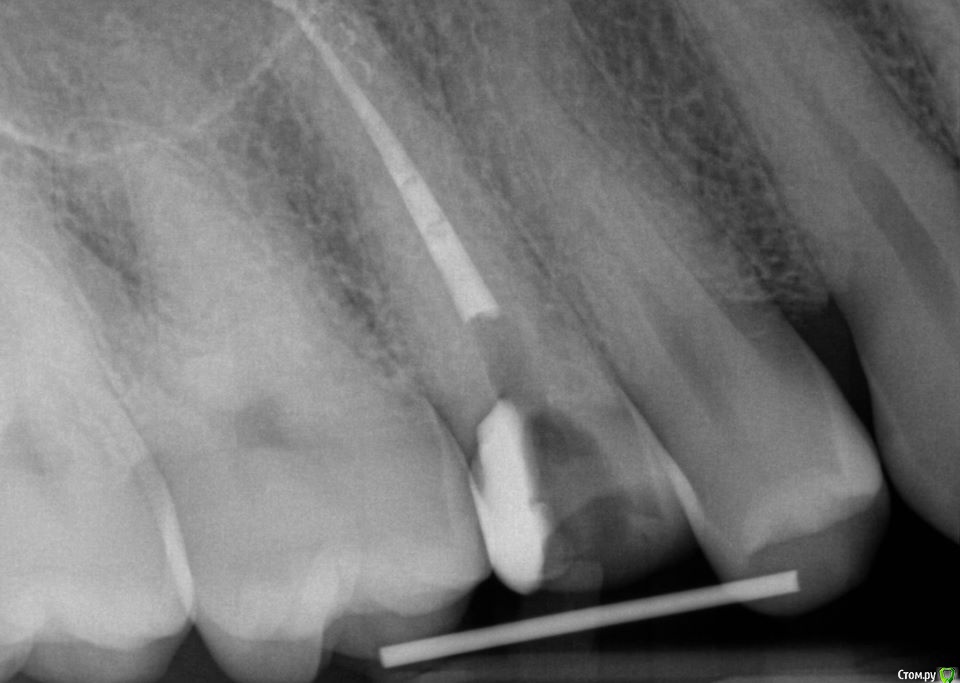

Kolchanov Опубликовано 23 июня, 2015 Поделиться Опубликовано 23 июня, 2015 Экструзия одиночного зуба для получения хоть какого-нибудь феррула. Подозреваю, что процедура не очень сложна и вполне модет быть освоена простым терапевтишкой, т.е. мной. Был бы очень благодарен, если бы кто-нибудь накидал своих мыслей по этому поводу, а еще лучше и фоток. И, конечно же, перечисление материалов. В одной из клиник, где я работаю, делают так иногда.После удаления штифтового зуба имеем поддесневой дефектhttp://s010.radikal.ru/i311/1506/49/4f3a03a5b53b.jpghttp://s010.radikal.ru/i313/1506/55/c752a532f478.jpgПациентка пожелала зуб сохранить. Теперь его тянут. И пятерочку еще в придачу.http://s014.radikal.ru/i327/1506/75/e9897bfb0e24.jpghttp://i024.radikal.ru/1506/99/1f1453b881ef.jpghttp://s017.radikal.ru/i434/1506/ea/caf4284659b4.jpghttp://s018.radikal.ru/i522/1506/ae/b2b54bddcdb8.jpghttp://s015.radikal.ru/i331/1506/7c/0efe752f8c35.jpgПока ничего сложного не вижу.У меня сейчас есть похожий случай. Но, послать в Москву... Не поедут. А на местного ортодонта как-то надежды мало. Я потом залью сюда фотки со своими мыслями. Может кто что присоветует...Спасибо! 1 Ссылка на комментарий

krokomot Опубликовано 23 июня, 2015 Поделиться Опубликовано 23 июня, 2015 Экструзия одиночного зуба для получения хоть какого-нибудь феррула. Подозреваю, что процедура не очень сложна и вполне модет быть освоена простым терапевтишкой, т.е. мной. Был бы очень благодарен, если бы кто-нибудь накидал своих мыслей по этому поводу, а еще лучше и фоток. И, конечно же, перечисление материалов. В одной из клиник, где я работаю, делают так иногда.После удаления штифтового зуба имеем поддесневой дефект Пациентка пожелала зуб сохранить. Теперь его тянут. И пятерочку еще в придачу. Пока ничего сложного не вижу.У меня сейчас есть похожий случай. Но, послать в Москву... Не поедут. А на местного ортодонта как-то надежды мало. Я потом залью сюда фотки со своими мыслями. Может кто что присоветует...Спасибо!Ох и любят у нас врачи заниматься вот таким лепиловом)))) Инженера в себе не скроешь)) Почему не с бреккетами? Приклеили несколько, дугу, цепочку проволку, что угодно, все же проще и предсказуемее (и быстрее) Ссылка на комментарий

Kolchanov Опубликовано 25 июня, 2015 Автор Поделиться Опубликовано 25 июня, 2015 (изменено) Вопрос такой - при ортоэкструзии обязательно нужно каждую неделю "подрезать" круговую связку? По теме есть вот такой кейс, автора к сожалению не помню.Это Григория (ForestDent) кейс. Связку надо обязательно резать, чтобы без кости вытягивался. Изменено 25 июня, 2015 пользователем Kolchanov 1 Ссылка на комментарий